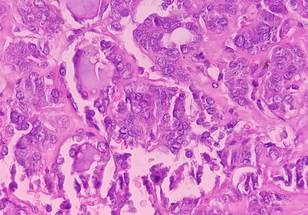

Axi-cel CAR T targets the CD19 molecule on large B-cell lymphoma cells. The ZUMA-7 trial demonstrated that axi-cel reduced the risk of disease progression, the need for new therapy, or death by 60% compared to standard therapy. Despite these positive outcomes in event-free survival and overall survival, some patients did not respond well to therapy or relapsed quickly after treatment.

A team of researchers led by Dr. Frederick L. Locke, chair of the Blood and Marrow Transplant and Cellular Immunotherapy Department at Moffitt Cancer Center, analyzed tumor gene expression patterns from patient samples and determined that a B-cell gene expression signature and CD19 protein expression were significantly associated with improved event-free survival for patients treated with axi-cel but not standard therapy. Patients with lower tumor cell levels of CD19 had gene expression patterns associated with immune suppression. These observations suggest that the tumor immune environment may play an important role in regulating axi-cel therapy and outcomes. In addition, biomarkers associated with improved outcomes to axi-cel therapy decreased as patients had more treatments, suggesting that receipt of axi-cel in earlier lines of treatment is essential to ensure better patient outcomes.